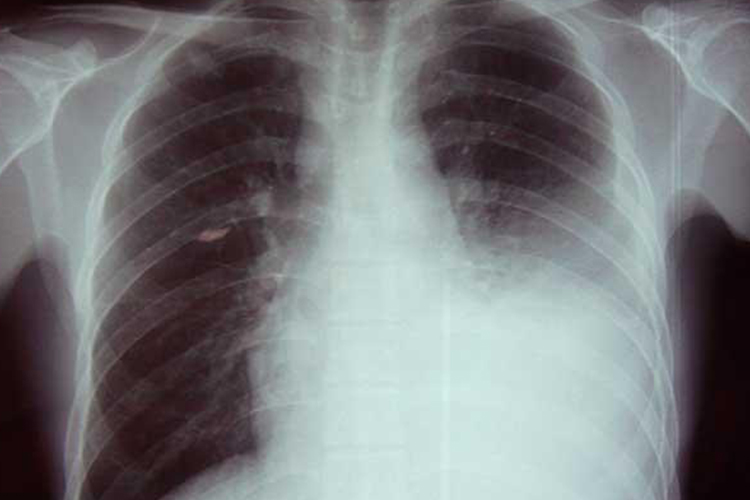

胸膜炎主要症状为胸痛,随深呼吸或咳嗽时疼痛加重,由于胸膜粘连、摩擦可出现针扎样疼痛,严重时可引起呼吸困难、面部青紫症状。

多是由于肺部感染侵及胸膜导致,胸膜发炎后可导致胸膜面粗糙,胸膜摩擦时可引起针扎样疼痛症状,由于胸膜与心脏位置相近,容易认为是心脏位置出现疼痛。